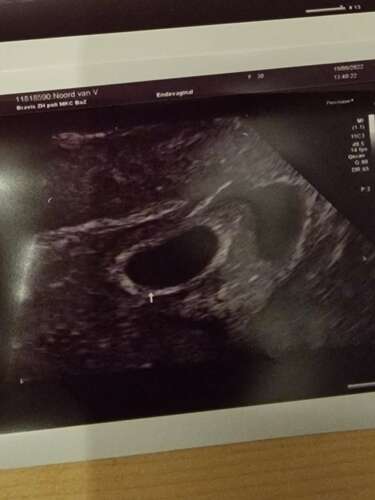

Had ik ook, deze is vanzelf opgelost. Eerstvolgende echo was hij kleiner, de keer daarop verdwenen

Is bij mij nu halve week geleden ontdekt. Verloskundige had de benaming ‘hematoom’ niet gebruikt zelfs. Kon opmaken dat ze het niet zo vaak tegenkomt. Nog geen bloeding. Ga er eigenlijk ook niet vanuit, omdat het achter de placenta zit. Geen adviezen om rustig aan te doen. Doe vanuit mezelf al rustiger aan vanwege lichte misselijkheid en moeheid. Maar wel nog flinke wandeling gemaakt nu op vakantie.

Heb ma 5 sept (termijn)echo. Heel benieuwd! Vandaag ook gewoon een workout gedaan. 😅 Had geen advies gekregen om rustig aan te doen. Hopelijk heeft de verloskundige die dat zei de juiste kennis erover. Kan zelf ook geen bewijs vinden dat rust de oplossing is voor zo’n klein hematoom (1x1cm). Morgen ga ik toch even met de vk bellen voor de zekerheid om te overleggen.

Ps: door de bloedingen was mijn hematoom bij 20 weken al voor de helft kleiner geworden, en is deze ondertussen niet meer zichtbaar op de echo.